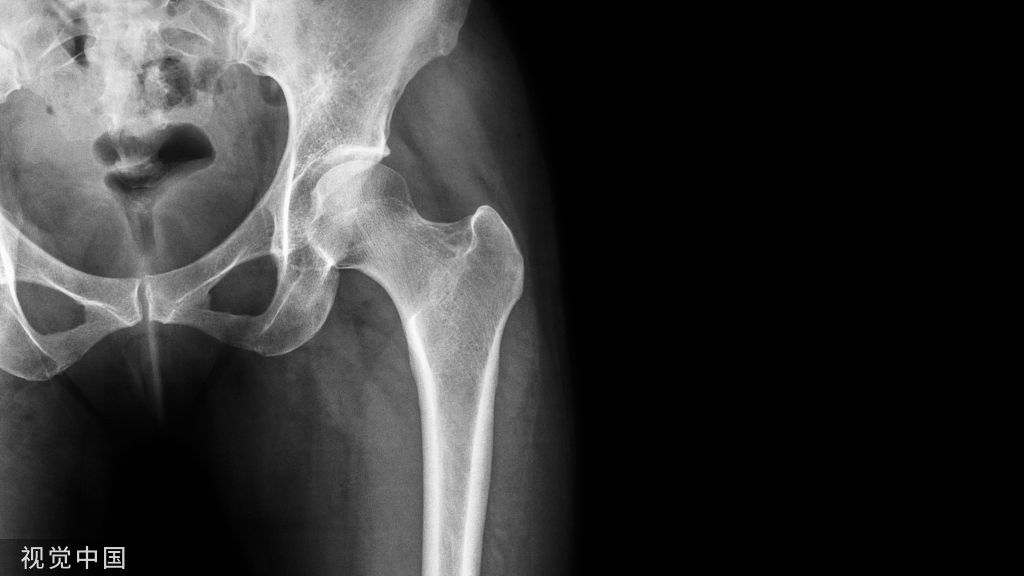

骨髓为造血干细胞(HSC)和骨髓间充质干细胞(bMSCs)提供了独特的微环境。HSC来源的破骨细胞和bMSCs衍生的成骨细胞通过持续的骨重塑活动来维持骨骼稳态介导。中枢神经系统(CNS)在调节外周器官的活动中发挥关键作用。中枢神经系统和免疫系统之间的长期相互作用使神经系统能够精确调节骨髓中的免疫环境。值得注意的是,交感神经可以通过调节HSC的扩增来应对创伤等生存压力。在骨折愈合的初始阶段,HSC产生多种免疫细胞并迁移到骨折间隙,介导血肿和骨痂的形成。临床实践发现,合并创伤性脑损伤(TBI)的骨折患者其骨折愈合速率显著加快,然而CNS损伤与TBI后骨愈合加速之间是否存在直接的神经免疫调控机制目前尚不清楚。

TBI可加速骨折愈合,但其潜在机制在很大程度上仍不为人知。越来越多的证据表明,中枢神经系统(CNS)在调节免疫系统和骨骼稳态方面起着关键作用。该研究发现TBI伴随交感神经张力显着升高,而化学交感神经切除术可阻断TBI诱导的骨折愈合,表明交感神经直接参与了TBI介导的骨折加速愈合。TBI诱导的肾上腺素能信号促进骨髓造血干细胞(HSC)的增殖,在骨折愈合的早期使造血活动向抗炎髓系扩增方向偏移。敲除β3或β2肾上腺素能受体(AR)可消除TBI介导的抗炎髓系细胞扩增和骨折加速愈合。这些研究表明,TBI通过交感张力重塑骨髓中的抗炎环境,在骨折愈合的早期阶段加速骨痂形成。值得讨论的是,焦虑等不良情绪造成的持续性交感神经兴奋往往被认为可直接作用于成骨细胞,抑制成骨活动并造成骨质丢失。而本研究揭示了交感神经切除会在骨折愈合的早期妨碍骨痂形成,表明交感神经的持续时间、强度、发生作用的生理/病理背景等因素,都会对生物学行为产生不同影响。因此,该研究揭示了肾上腺素能信号在骨折愈合早期的重要作用,对开发新型骨折愈合药物具有十分积极的意义。